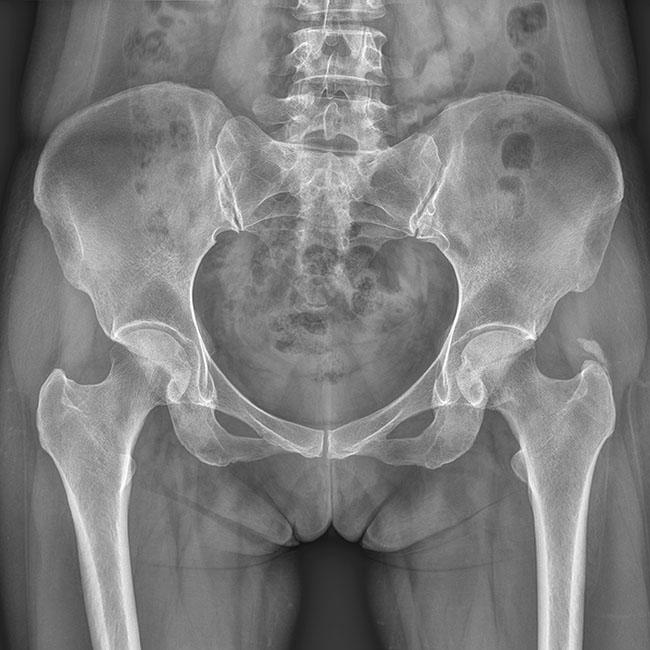

臨床樣本